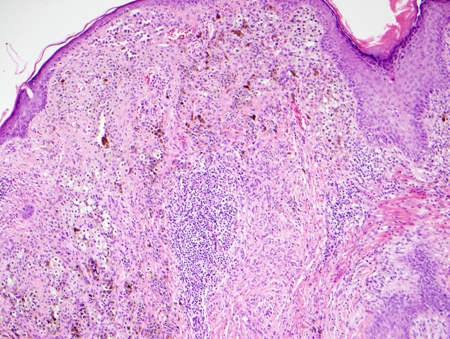

Photomicrograph of Clark's level IV invasive melanoma

From the personal collection of Dr Hobart Walling and Dr Brian Swick.